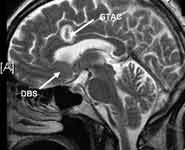

Press release issued 24 January 2011 - Pioneering neurosurgical treatment, a world first in Bristol, which very accurately targets brain networks involved in depression, could help people who suffer with severe and intractable depression. The research led by Dr Andrea Malizia, Consultant Senior Lecturer in the School of Social and Community Medicine at the University of Bristol and Mr Nikunj Patel, Senior Clinical Lecturer in the Department of Neurosurgery at North Bristol NHS Trust , are pioneering a number of treatments including experimental antidepressants, deep brain stimulation (DBS) and stereotactic neurosurgery. The patient, whose illness had stopped responding to conventional treatments, was offered DBS in the first trial in the world that stimulates two different brain networks that are involved in depression. DBS in this case provided some temporary response but was not sufficient to make her well. She is now well following further advanced stereotactic neurosurgery carried out in early 2010. The personal history of the patient, whose life has been changed by the pioneering treatment, will be broadcast on BBC One?s Inside Out West tonight [Monday 24 January]. Deep brain stimulation consists of inserting thin wires in the brain that are connected to a 'pacemaker'.